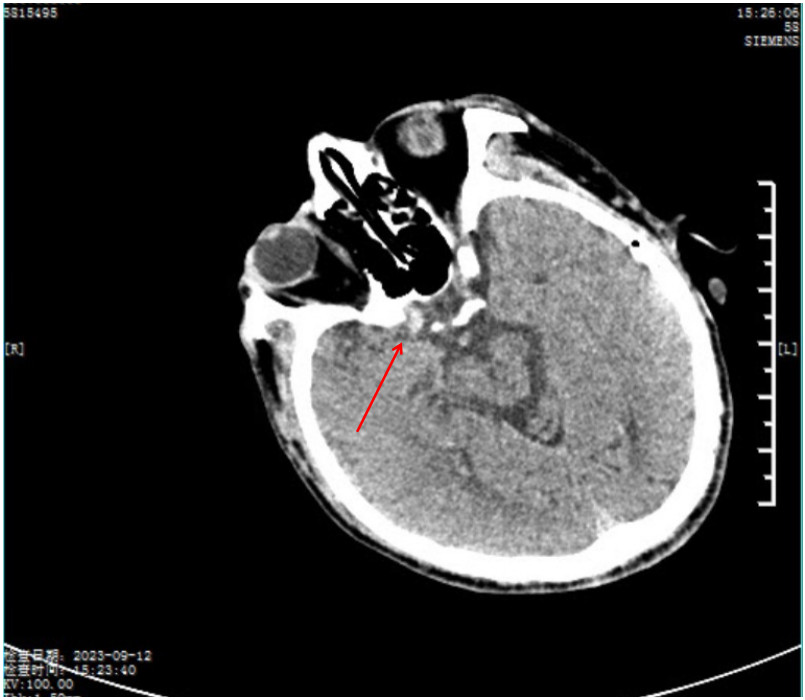

1 病例资料患者56岁男性,因“胸闷、大汗、左侧肢体活动障碍3 h”于2023-09-12入院。入院当日13:20患者突发胸闷大汗、左侧肢体完全不能动弹,15:12至急诊时神志不清。患者既往患高血压病10年,否认烟酒嗜好,否认家族遗传性疾病史。查体:血压120/80 mmHg(1 mmHg=0.133 kPa),神志模糊,两肺无啰音,心率70次/min,心律齐,无杂音,四肢肌力检查不配合,左侧肢体肌张力低,右侧肢体肌张力正常,左侧巴氏征阳性,右侧巴氏征阴性。随机血糖8.34 mmol/L,18导联心电图:窦律,下壁、右室导联ST明显抬高(图 1A、B),心肌酶的肌钙蛋白I:0.038 ng/mL(参考值0~0.034 ng/mL),头颅CT示无脑出血,可见右侧颈内动脉末端高密度征(图 2),提示颈内动脉远端存在血栓。

| 图 2 患者入院头颅CT(红色箭头为右侧颈内动脉末端高密度征) |